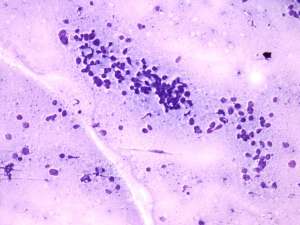

Cytology: suspicion of non Hodgkin lymphoma.

Biopsy was performed from the lesion and histopathology revealed large B cell lymphoma.

The cytological picture was identical with a small cell malignant tumor. Differential diagnostics included a metastatic small cell lung tumor and malignant lymphoma. The clinical presentation substantially decreased the likelihood of the former.